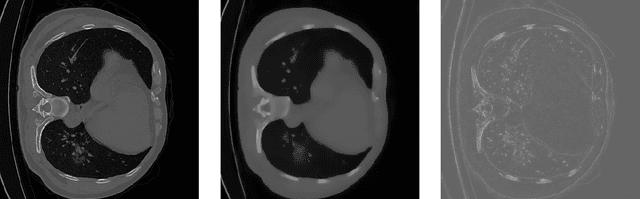

Abstract:The novelty of the COVID-19 disease and the speed of spread has created a colossal chaos, impulse among researchers worldwide to exploit all the resources and capabilities to understand and analyze characteristics of the coronavirus in term of the ways it spreads and virus incubation time. For that, the existing medical features like CT and X-ray images are used. For example, CT-scan images can be used for the detection of lung infection. But the challenges of these features such as the quality of the image and infection characteristics limitate the effectiveness of these features. Using artificial intelligence (AI) tools and computer vision algorithms, the accuracy of detection can be more accurate and can help to overcome these issues. This paper proposes a multi-task deep-learning-based method for lung infection segmentation using CT-scan images. Our proposed method starts by segmenting the lung regions that can be infected. Then, segmenting the infections in these regions. Also, to perform a multi-class segmentation the proposed model is trained using the two-stream inputs. The multi-task learning used in this paper allows us to overcome shortage of labeled data. Also, the multi-input stream allows the model to do the learning on many features that can improve the results. To evaluate the proposed method, many features have been used. Also, from the experiments, the proposed method can segment lung infections with a high degree performance even with shortage of data and labeled images. In addition, comparing with the state-of-the-art method our method achieves good performance results.